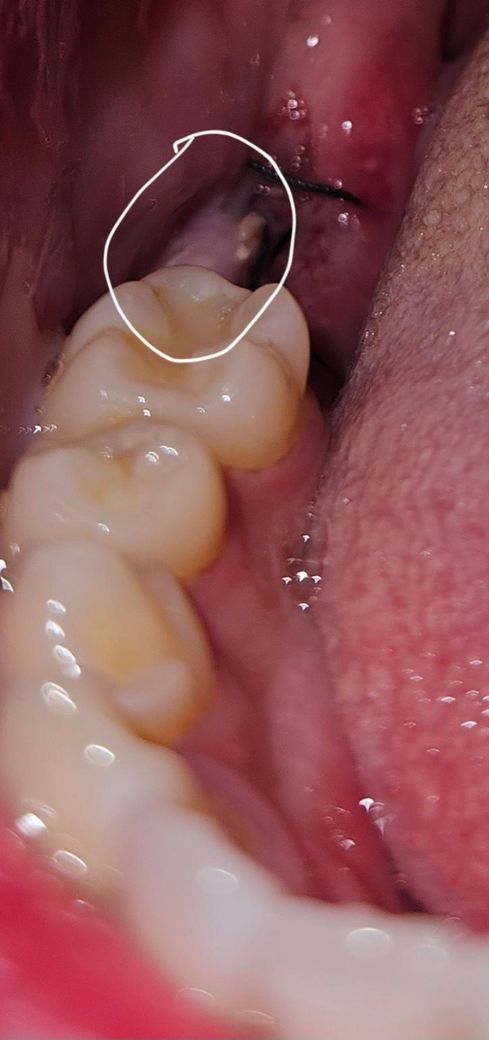

사랑니,어금니 2개발치 6일차인데 잇몸 염증인가요?

사진으로는 핑크색? 부위인데요 (조그만한건 음식물이겠죠..)

사랑니, 그앞어금니 2개를 발치했습니다

발치 부위는 별이상 없는거 같은데 왜 그 사이 벽쪽에 저런게 생긴건가요? 혀로 살짝 건드려보니 물컹해요

통증은 없는데 이물감이 있네요.

보통 하얀색으로 덮이는건 치유조직이라는데 저기는 발치부위가 아니라 걱정되네요

월요일에 실밥은 풀기로 했습니다.

염증, 육아조직을 비롯해 치유과정에서 생기는 다양한 잇몸 변화같습니다 위생관리 잘해주세요